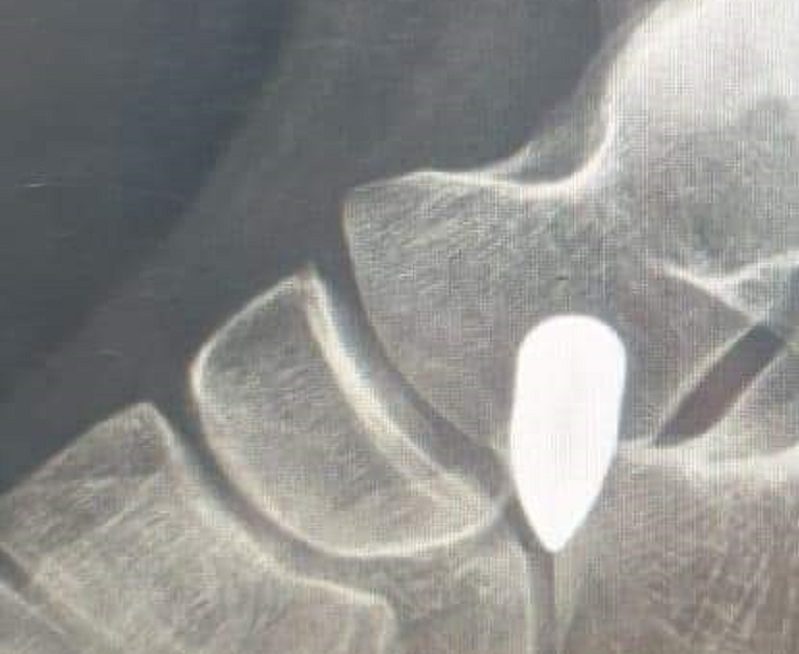

أصيبت الطفلة دعاء ع. من بلدة وادي الجاموس، العكارية، برصاصة طائشة في ظهرها، بينما كانت برفقة والدتها، عند أقربائها في ببنين. وقد تم نقلها الى مستشفى الخير للعلاج.

وأفادت معلومات الجديد أن “الطفلة أصيبت، جراء اطلاق نار، بسبب اعلان النتائج الرسمية للشهادة التعليم المهني”.